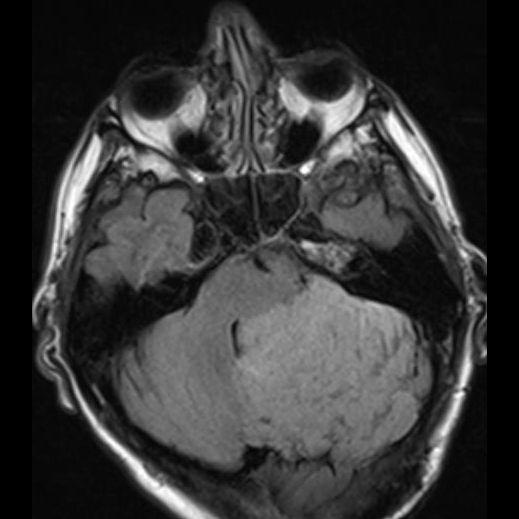

24 yaş, E

Baş ağrısı

Lhermitte duclos

Lhermitte-Duclos hastalığı (Dysplastic cerebellar gangliocytoma)

Dysplastic cerebellar gangliocytoma(Lhermitte-Duclos hastalığı)

Lhermitte-Duclos hastalığı

Displastik serebellar gangliositoma